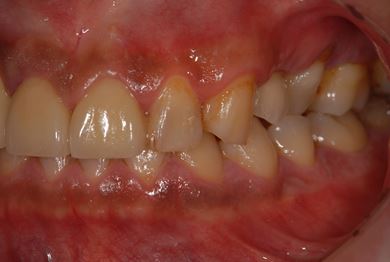

インプラントの症例写真 IMPLANT

抜歯即日スピードインプラント治療

| 性別/年齢 | 男性 / 36歳 | ||||||||||||||||||||||||||||||||

| 主訴 | 歯が折れているので、インプラントにしたい。 | ||||||||||||||||||||||||||||||||

| 治療方針 | 抜歯と同時にインプラント埋入を行い、治療期間を短縮する。 | ||||||||||||||||||||||||||||||||

| 治療内容 | インプラント2本(抜歯即日インプラント治療)、ジルコニアフレームオールセラミッククラウン1本、オールセラミッククラウン2本(セラミック用土台2本)、メタルボンドセラミッククラウン1本 | ||||||||||||||||||||||||||||||||